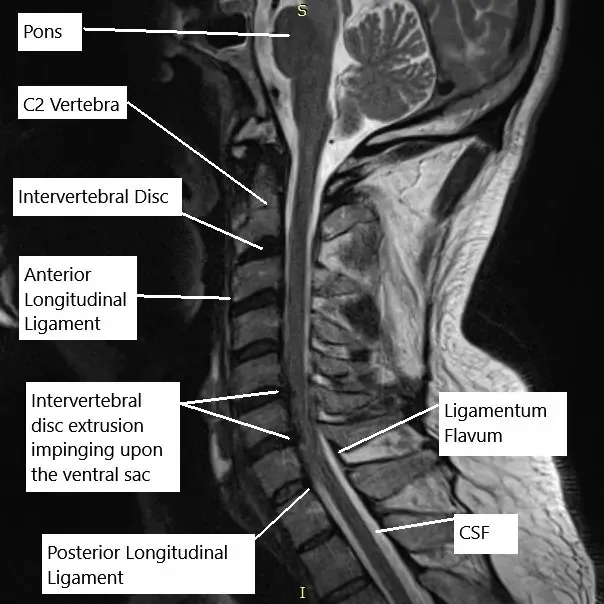

Resonancia magnética de la columna cervical en la sección sagital.

El examen físico corroboró los hallazgos de la resonancia magnética de la columna cervical, que sugerían que en C5-C6 hay un complejo osteofito de disco posterior. Hay una estenosis grave del canal espinal y una hipertrofia bilateral de la articulación uncovertebral. Hay estenosis neural foraminal derecha y foraminal neural izquierda de moderada a severa.

En C6-C7, hay una hernia/extrusión del disco paracentral izquierdo que crea una impresión en la parte ventral del saco tecal y la médula espinal. Hay estenosis grave asociada del canal espinal y hipertrofia bilateral de la articulación uncovertebral. Existe una estenosis foraminal neural del lado izquierdo severa.